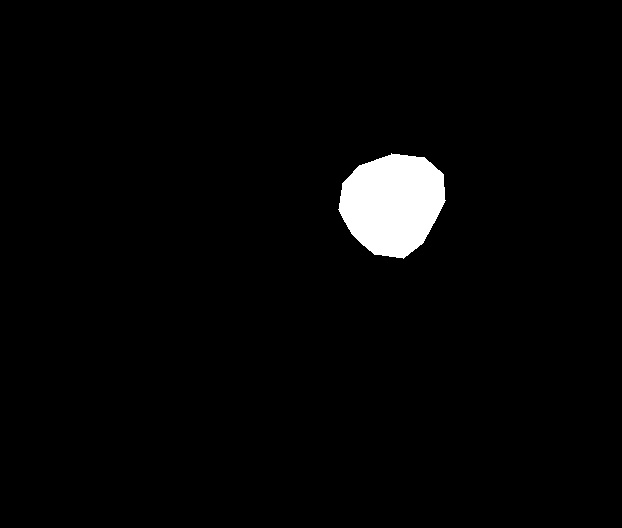

We have used a polyp dataset published with HyperKvasir dataset [51], which consists of polyp findings extracted from endoscopy examinations. HyperKvasir contains polyp images with corresponding segmentation masks annotated by medical experts. We use only this polyp dataset as a case study because of the time and resource-consuming training process of the SinGAN-Seg pipeline. However, the SinGAN-Seg model and pipeline can be used for any segmentation dataset.

A few sample images and the corresponding masks of the polyp dataset in HyperKvasir are shown in Fig 2. The polyp images are RGB images. The masks of the polyp images are single-channel images with white () for true pixels, which represent polyp regions, and black () for false pixels, which represent clean colon or background regions. In this dataset, there are different sizes of polyps. The distribution of polyp sizes as a percentage of the full image size is presented in the histogram plot in Fig 3, and we can observe that there are more relatively small polyps compared to larger polyps. Additionally, a subset of this dataset was used to prove that the performance of segmentation models trained with small datasets can be improved using our SinGAN-Seg pipeline, and the whole dataset was used to show the effect of using SinGAN-Seg generated synthetic images instead of a large dataset which has enough data to train segmentation models. In this regard, this dataset was used for two purposes: